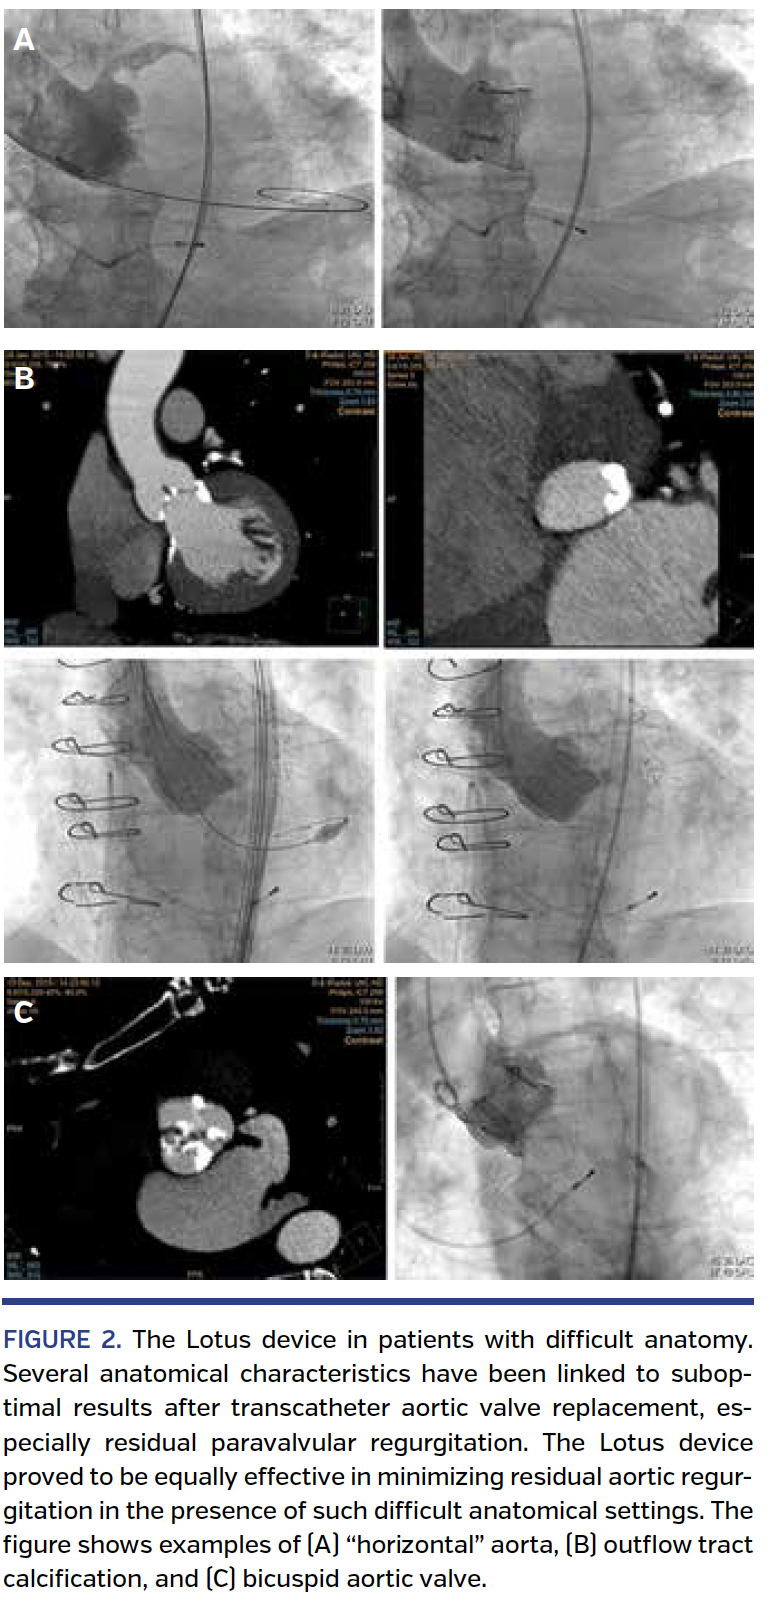

The Lotus device in specific patient subsets with difficult anatomy. Several anatomical conditions have been related to suboptimal results after TAVR implantation. Among them are a nearly horizontal aorta, significant outflow tract calcifications, or bicuspid valves.16-18 In 13 of our patients, the angle between the annular plane and the horizontal plane was ≥60° and in 4 of the patients it was >65°. Again, significant (more than mild) postinterventional aortic regurgitation was not observed in any of these patients (Figure 2A). Significant left ventricular outflow tract calcifications were present in 11 Lotus cohort patients. More than mild postinterventional aortic regurgitation was not present in any of these 11 patients (Figure 2B). Finally, 2 patients with true bicuspid aortic valve anatomy were implanted with the Lotus device in our series with excellent postinterventional results (Figure 2C).

The mechanically expanded, fully repositionable transfemoral Lotus device has been recently introduced into real-world practice. Preliminary studies like the REPRISE trials have shown promising results.12,13 Here, we report our first single-center real-world experience with this device in 63 patients and include VARC-2 defined short-term outcomes. The device proved to give excellent results with respect to postinterventional aortic regurgitation, a pacemaker rate of roughly one-third, and a reasonable safety profile. In patients with difficult anatomy prone to device malfunction like horizontal aorta, bicuspid anatomy, or outflow tract calcification, procedural results were similar, especially with respect to postinterventional aortic regurgitation.

Since the implementation of the TAVR procedure in daily routine, many devices have been evaluated in early clinical studies and introduced into real-world practice. Among them, the Edwards Sapien 3 and the CoreValve Evolut R represent two types of third-generation devices with improved abilities to reduce paravalvular regurgitation, pacemaker rate, and ease of implantation.9,19 Their preceding valve designs (the CoreValve and Sapien XT) have already demonstrated excellent results in large-scale clinical studies in comparison with the conservative approach as well as the surgical approach in high-risk patients with symptomatic severe aortic stenosis.1-5 The Lotus device adds two new features to the TAVR device landscape. First, it is a fully repositionable device, which means that complete deployment and assessment of device success is possible prior to release of the device. Second, it includes a paravalvular sealing feature (adaptive seal) that should help to achieve device success even in patients with heavy calcification in the absence of the risk of annular rupture due to aggressive postdilation. Both features make the Lotus device particularly useful in the setting of difficult anatomies like horizontal aorta, outflow tract calcification, or bicuspid valve, which are all prone to device malfunction, especially with self-expanding valves.16-18 In our cohort, such anatomic conditions were present in one-third of the patients. However, results with respect to postprocedural aortic regurgitation were equally excellent when compared with patients who had less difficult anatomies. Of note, repositioning of the device at least once during the procedure was necessary in more than one-fourth of the patients, indicating the value of this feature to achieve optimal hemodynamic results.